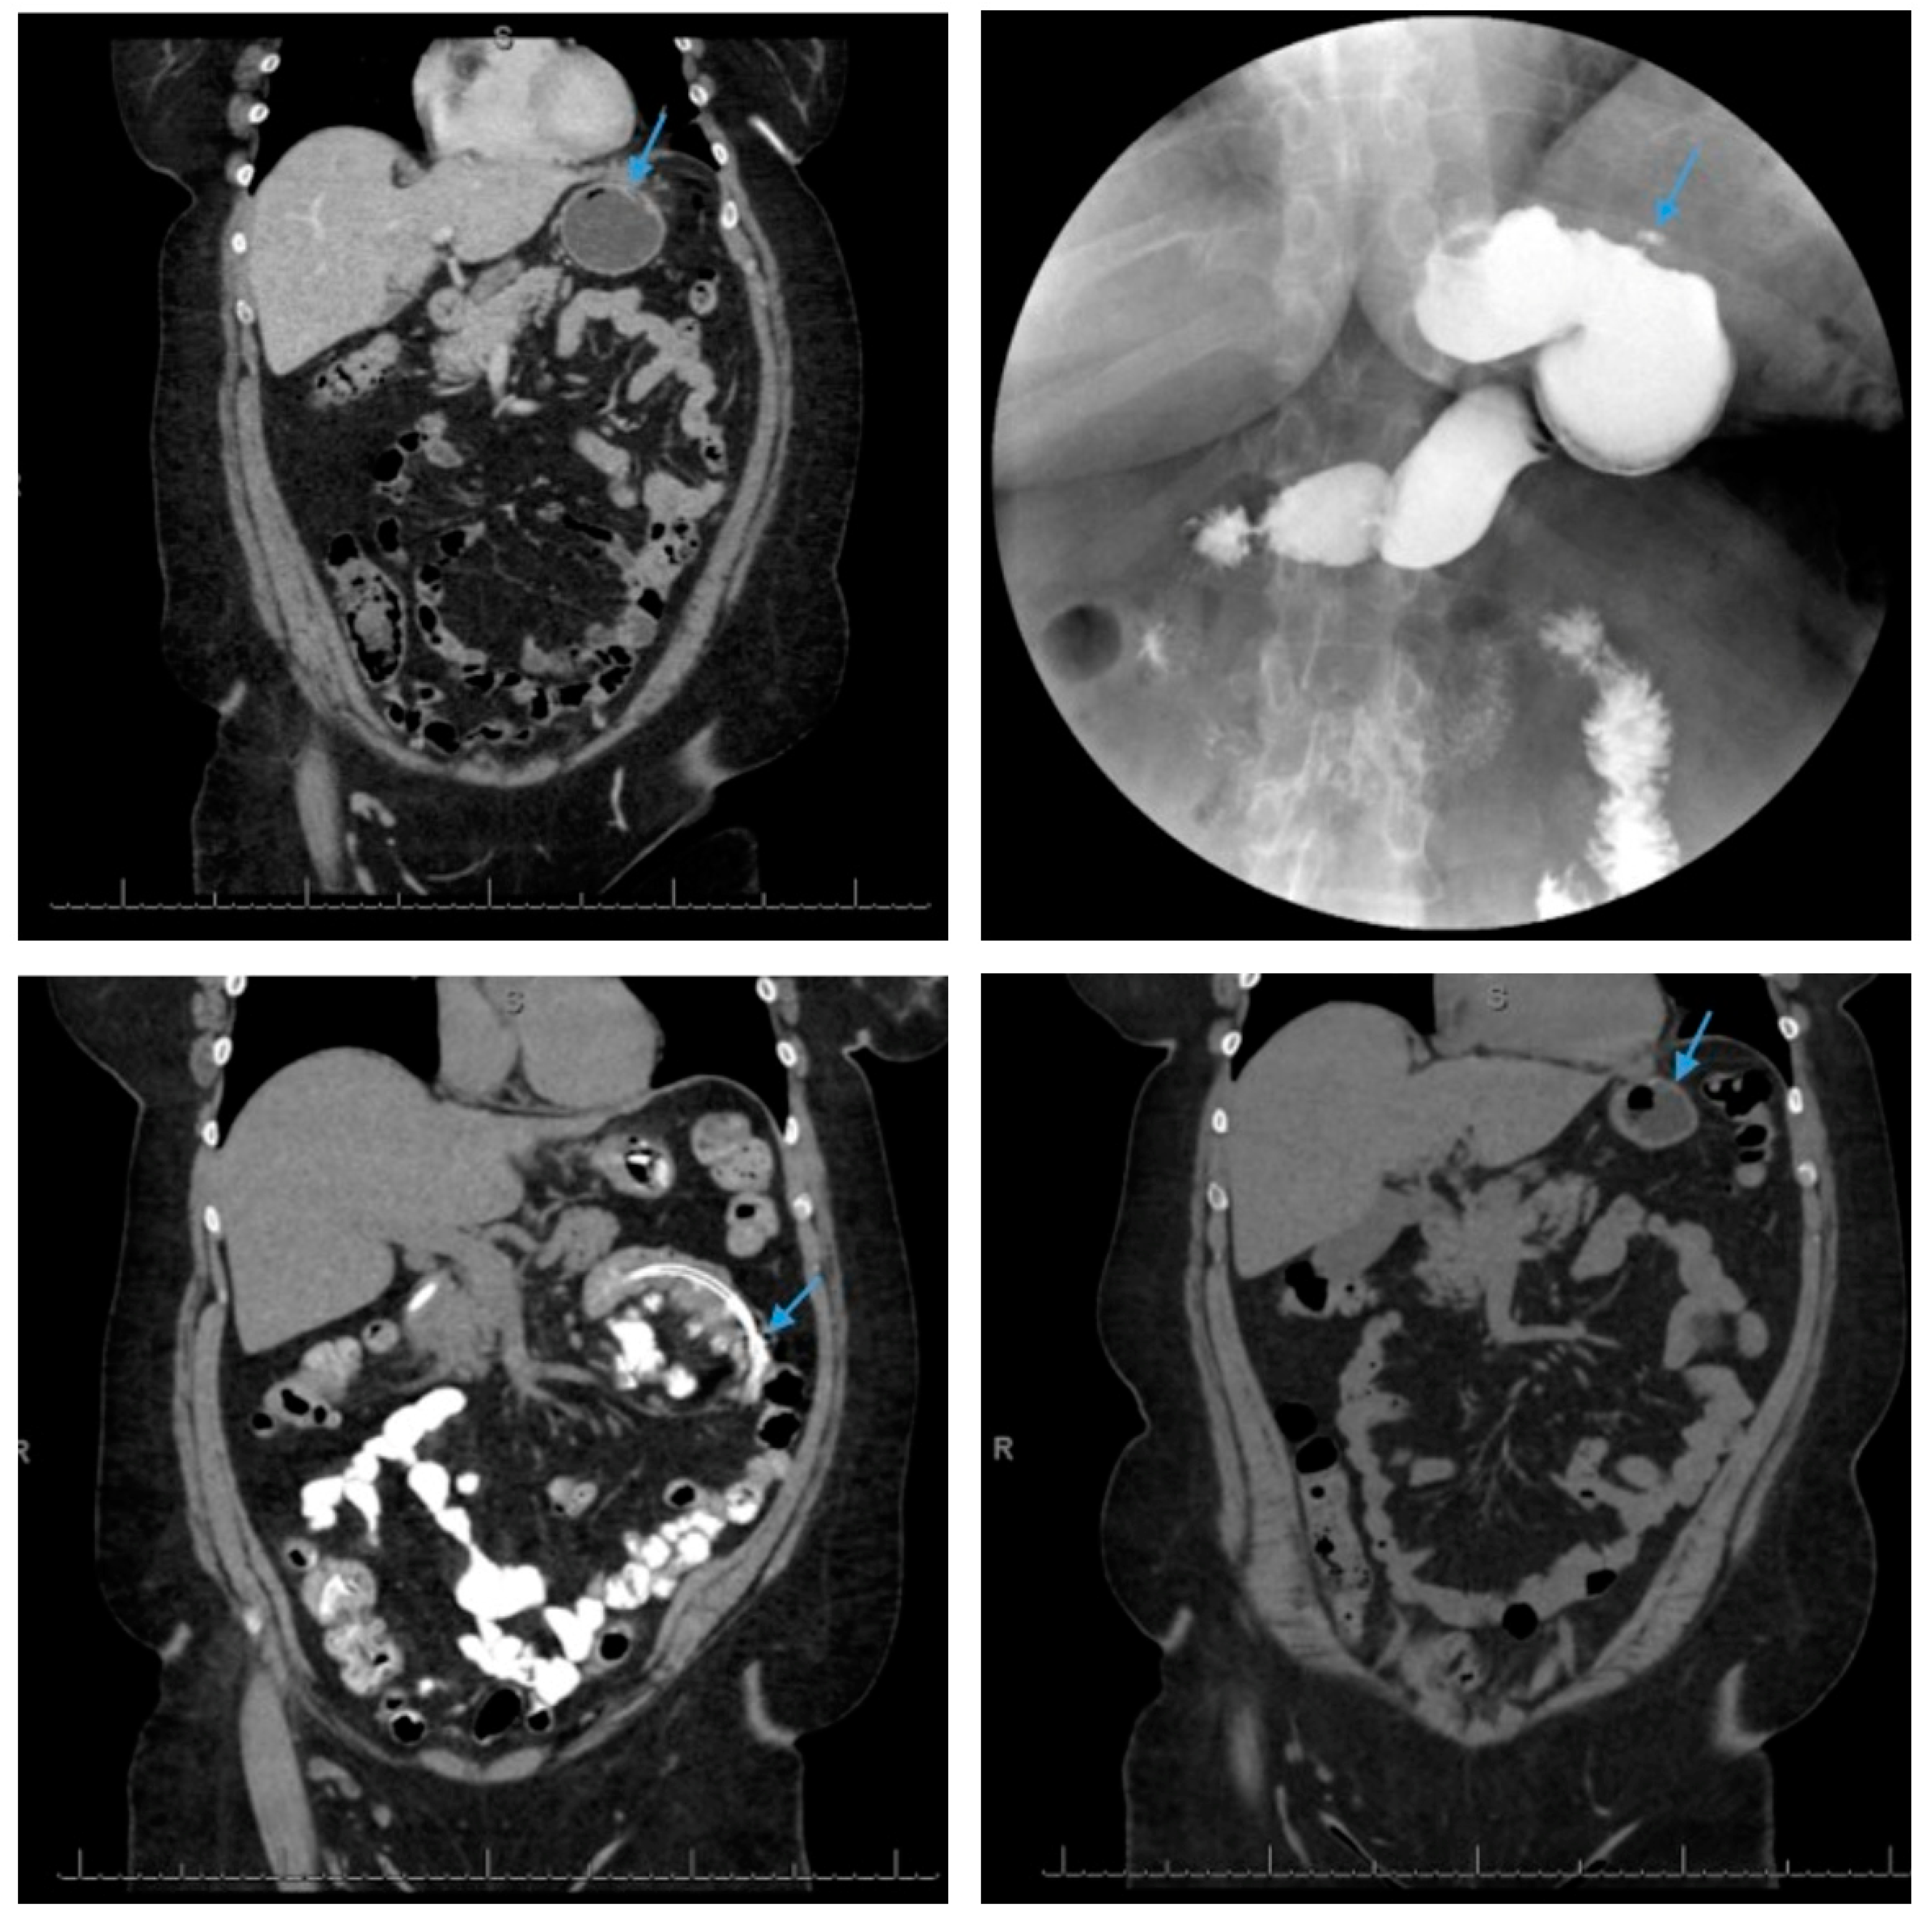

Coronal view of a computed tomography scan of the abdomen and pelvis reveals a small, contained leak (arrow, top left) along the greater curvature of the gastric body in a patient following sleeve gastrectomy. Upper gastrointestinal series demonstrates a small amount of extravasated contrast along the greater curvature of the gastric body with no free spill of extravasated contrast which is consistent with a small, contained perforation (arrow, top right) in a patient post-sleeve gastrectomy. The patient was treated with nothing per os and nasojejunal tube feeds (arrow, bottom left) for two weeks, with the resolution of sleeve leak and the removal of the nasojejunal tube (arrow, bottom right) as demonstrated on a follow-up coronal view of a computed tomography scan of the abdomen and pelvis.

Axial view of a computed tomography scan of the abdomen and pelvis with contrast reveals a uniform, thin-walled, cystic lesion of the pancreas, which measures 90 mm × 52 mm × 48 mm, with peripheral calcifications with a BMI of 38 (arrow, A). Endoscopic ultrasound demonstrates an anechoic and hypoechoic lesion of the pancreatic body with two compartments, no septae or internal debris, and an associated mural nodule which was suggestive of a mucinous cystic neoplasm (arrow, B). The patient subsequently underwent a laparoscopic sleeve gastrectomy and a concurrent, open distal pancreatectomy which was complicated by a persistent pancreatic leak as well as a gastric sleeve leak (blue arrow, C) as demonstrated by contrast injected through a percutaneous drain (silver arrow, C). The percutaneous drain is redemonstrated on upper endoscopy (arrow, D). Note the additional percutaneous drain in the pancreatic bed for the postoperative leak (green arrows, C,G). Endoscopic internal drainage using transgastric double-pigtail stents was performed as demonstrated on fluoroscopic imaging (arrows, E,G) and endoscopy (arrow, F). After a prolonged course, the patient had a complete recovery, and a follow-up CT scan of the abdomen and pelvis confirmed the resolution of the leak and the removal of the double-pigtail stents and percutaneous drains (H).